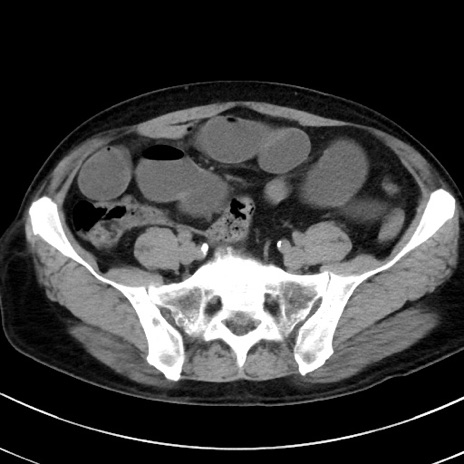

症例38(横断像)

【症例】70歳代 男性

【主訴】腹痛・嘔吐

【現病歴】昨晩より、嘔吐・腹痛あり。今朝になっても嘔吐あり。来院。

【既往歴】心臓バイパス手術、開腹胆摘、腸閉塞

【身体所見】BP 107/71mmHg、HR 116/min、腹部:平坦、軟、下腹部に軽度圧痛あり。反跳痛なし。

【データ】WBC 15100、CRP 0.32